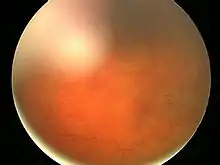

| Fundal photograph showing severe papilledema in the left eye | |